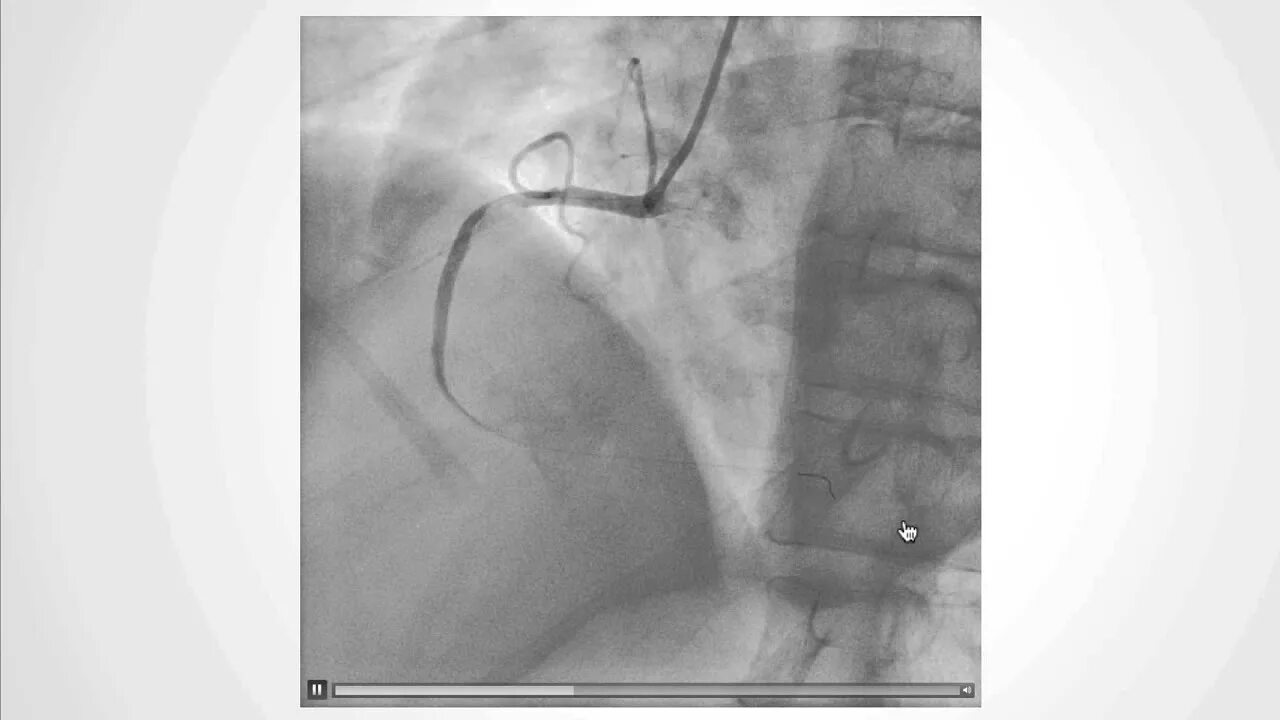

No reflow феномен